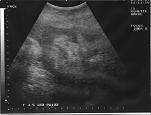

Ronette is now two weeks past her estimated due date. Due to her size and lack of any regular labor, her midwife requests that she take a biophysical profile. This ultrasound exam will provide information such as estimated size of the baby, general health of the placenta, and the baby's position in the womb. We are told that Katherine is estimated to be over 12 pounds and that the amount of amniotic fluid is borderline low. However, the worst news we received was that Katherine is now posterior (i.e. facing forward). If we are going to expect any success in our homebirth, we would need to get Katherine to turn over.

Katherine's ultrasound at 42 weeks. Say cheese....